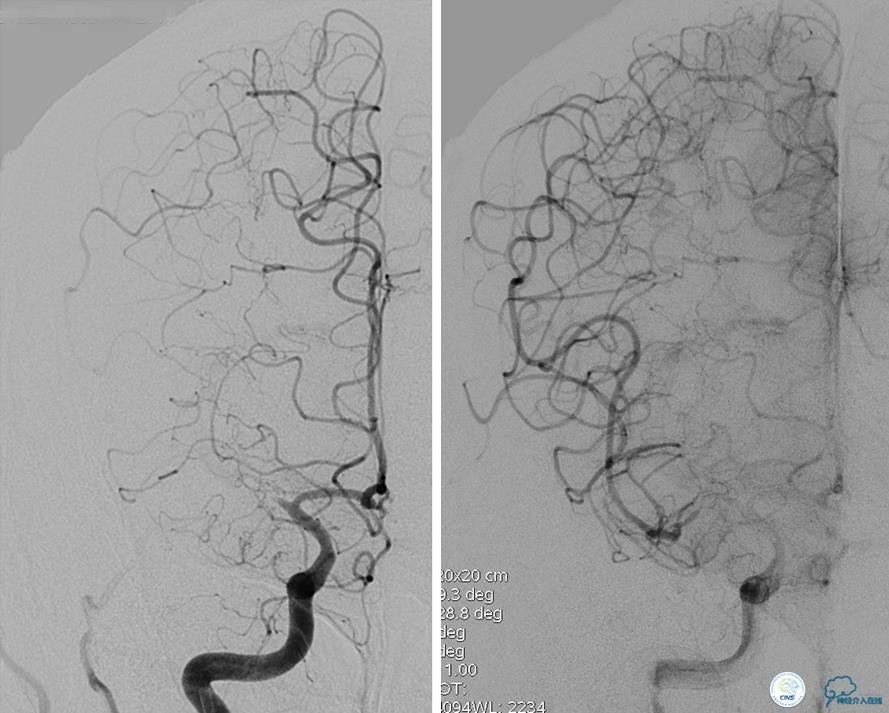

病例5

患者:49岁男性,左侧偏瘫1个月,药物治疗、康复训练效果不好,转我院,肌力0~1级。

core-clilnical明显不匹配,是介入开通的合适患者。

造影评价血管、判断闭塞段,微导丝谨慎穿过闭塞段,微导管造影,交换技术,球囊扩张,Enterprise支架。在后扩张时导丝刺破M3段血管,蛛网膜下腔出血(SAH)。

微导管进入破裂血管,栓塞弹簧圈1枚,出血停止,结束手术。继续双抗,术后2天肌力2级,神经功能恢复明显加快。

术后即刻和6天后CT,患者无明显临床症状。

半年后复查造影,无支架内再狭窄,可见弹簧圈,患者恢复至自己柱杖行走。